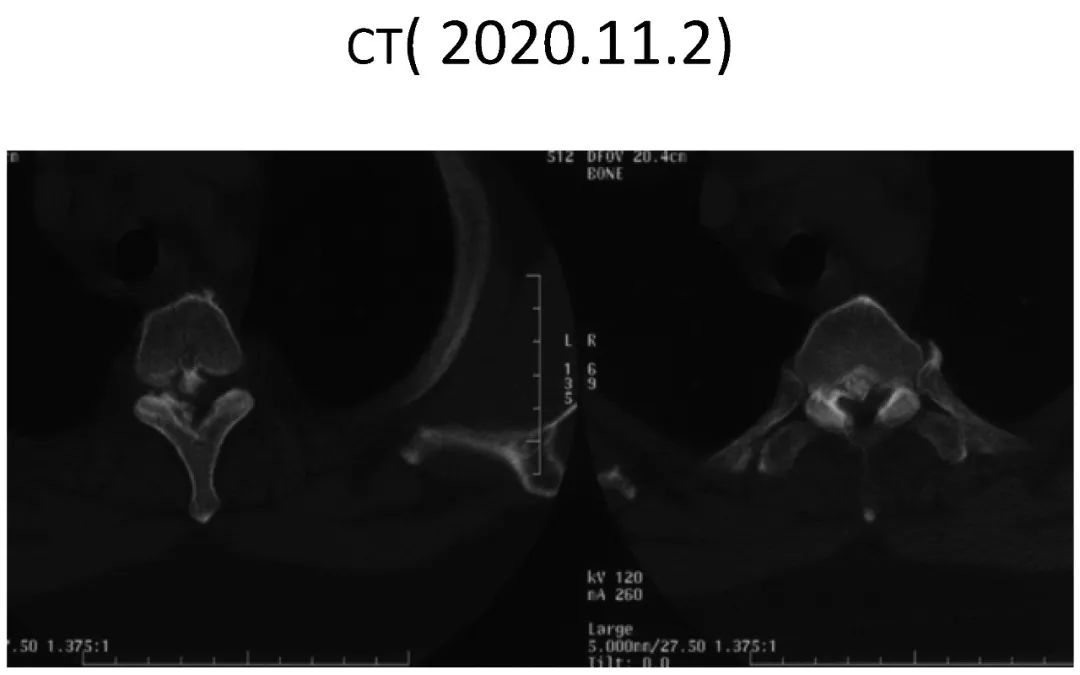

影像资料:

Thoracic spinal stenosis(T2-T3)